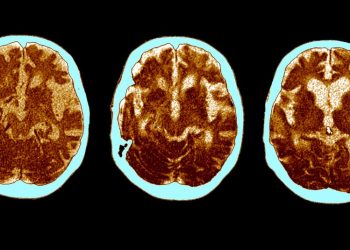

El cerebro de los supervivientes de una forma grave de covid-19 envejece 20 años, dice un nuevo estudio

2022-05-04 Nuevo Mundo - 96.1 El impacto que tiene sobre la capacidad cognitiva haber sufrido un...